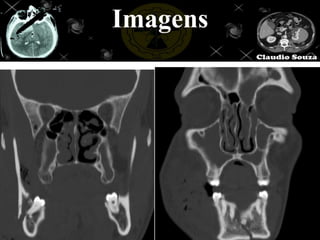

Técnica

Imagens reformatadas

Bone                Mole

Imagens pós reformatação